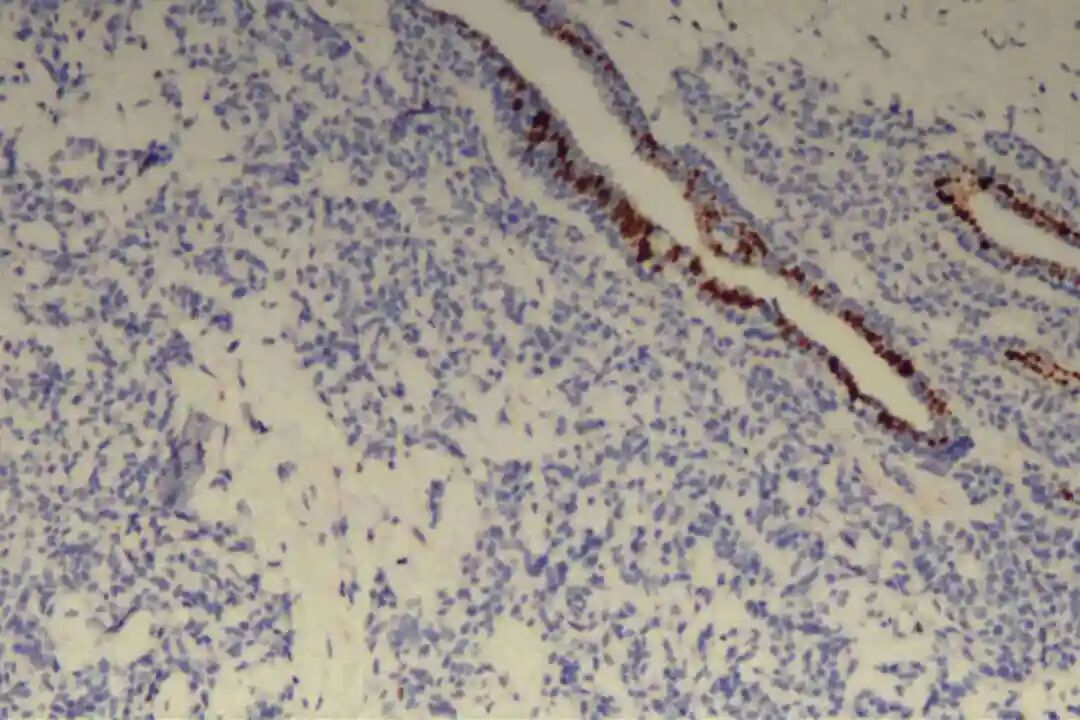

此外,肿瘤细胞不表达神经内分泌标志物(CgA、Syn、CD56),可排除神经内分泌肿瘤;不表达GCDFP-15,可排除大汗腺来源肿瘤;基底膜物质(Ⅳ型胶原、laminin)阳性,主要分布于筛状结构、管状结构的腔隙周围及实性巢团的微小腔隙内,进一步支持PACC的诊断。

免疫组化:09号片:ER(-),PR(-),Her-2(2+),CK7(腺上皮+),CD117(+),CK5/6(肌上皮+),P63(肌上皮+),GCDFP-15(-),GATA3(-),S-100(+,显示神经侵犯),P120(膜+),E-Cadherin(膜+),P53(野生表型),Ki67(+)10%。